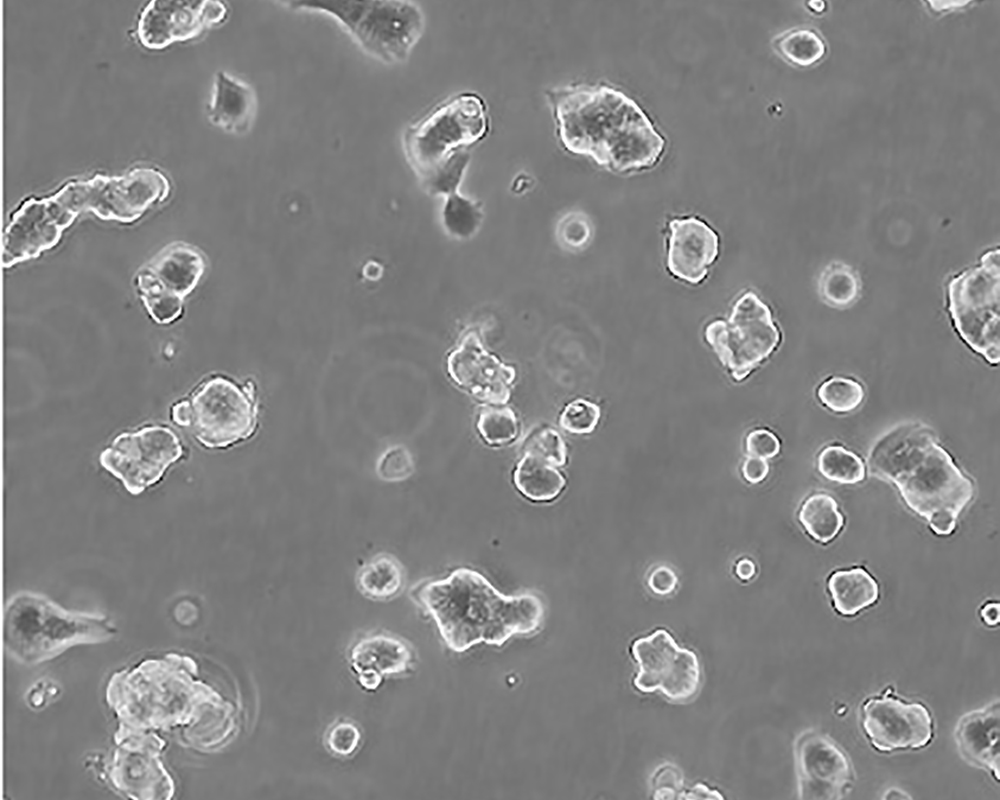

ZR-75-1 [ZR751]

產品名稱 ZR-75-1 [ZR751]

中文名稱 人乳腺癌細胞

組織來源 浸潤性導管癌;腹水轉移;女性

生長特性 adherent

形態特征 epithelial

細胞描述 該細胞產生高水平的黏液素MUC-1 mRNA,低水平的MUC-2 mRNA,但不表達MUC-3基因;表達雌激素受體。